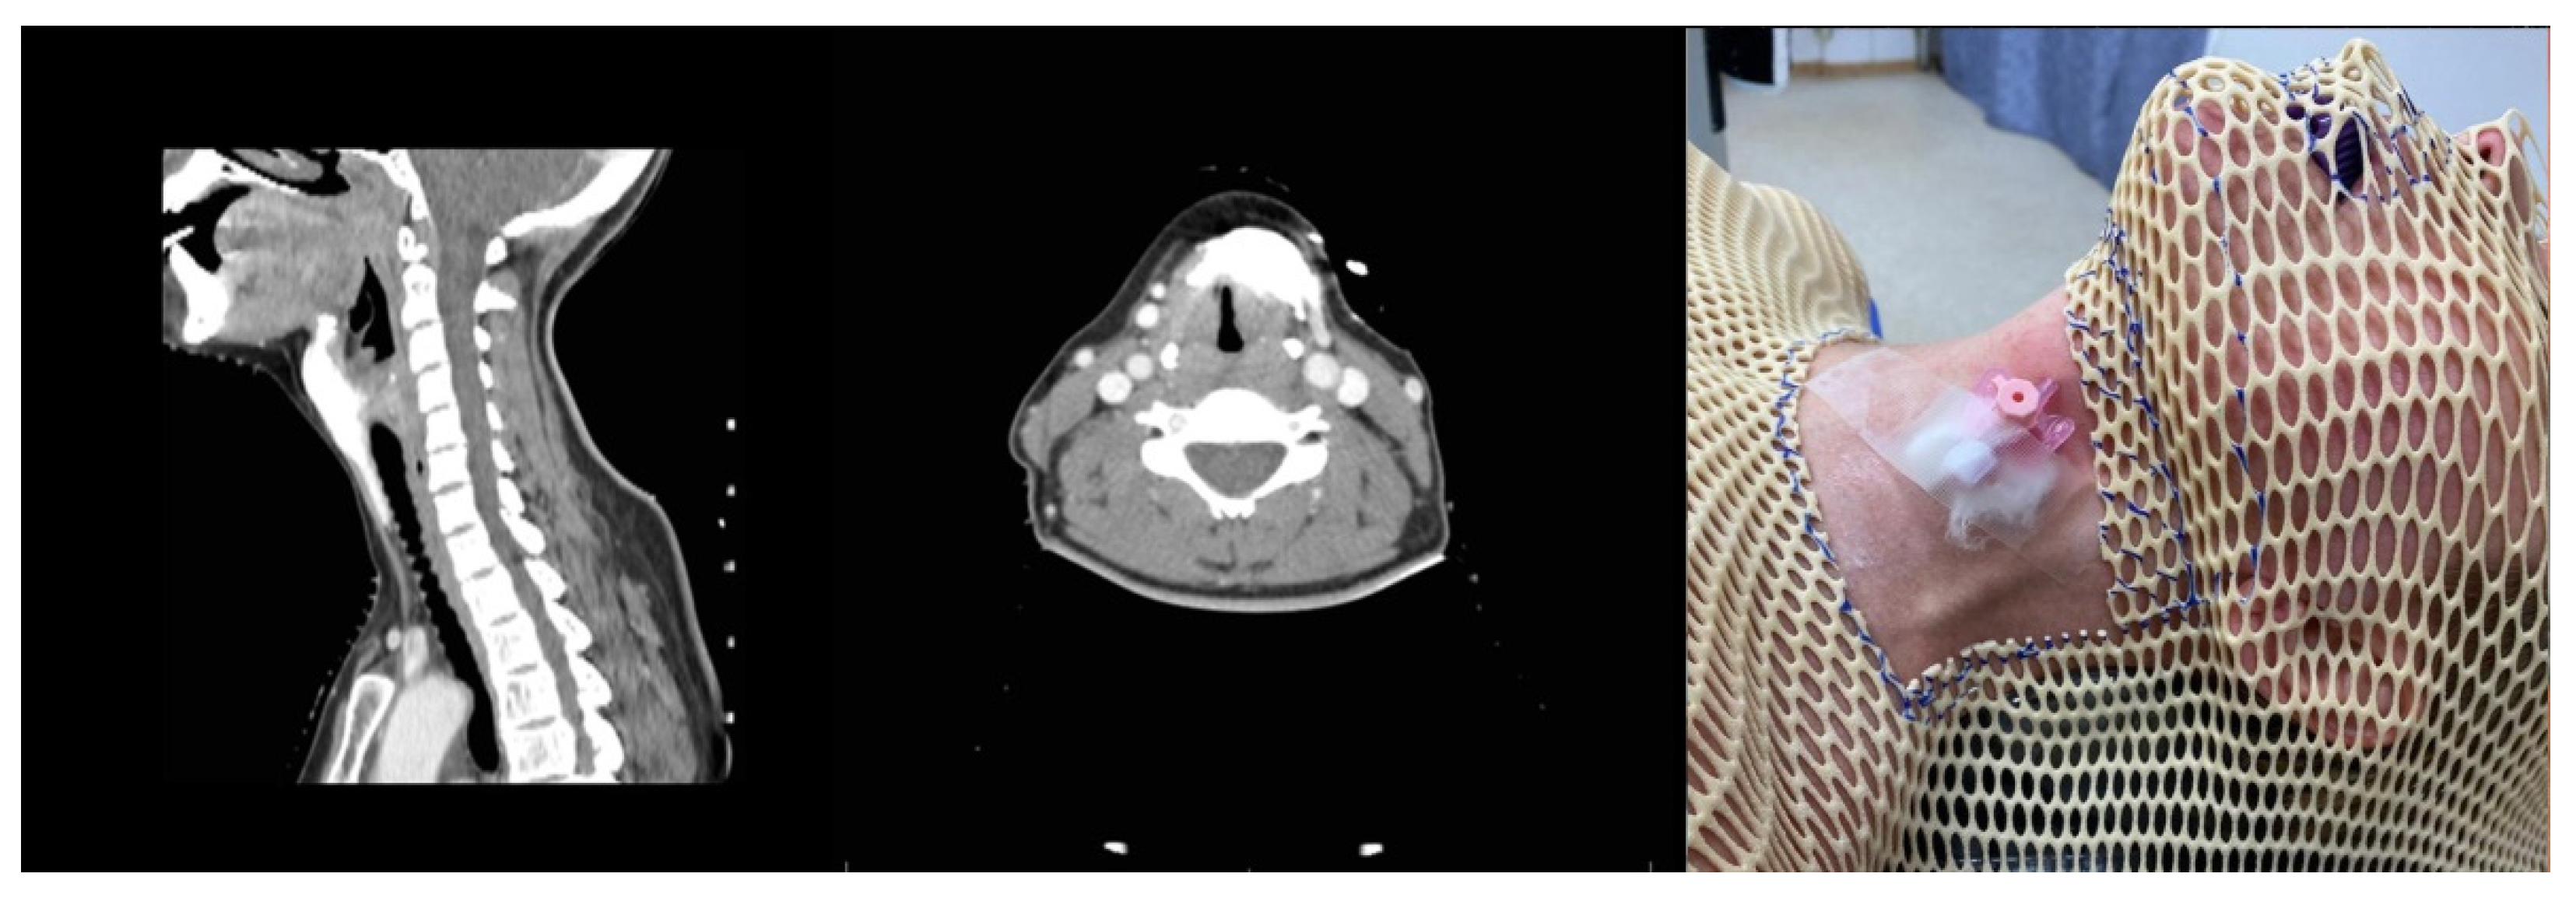

3.1. Case 1. Fixation Mask

Developed Approach